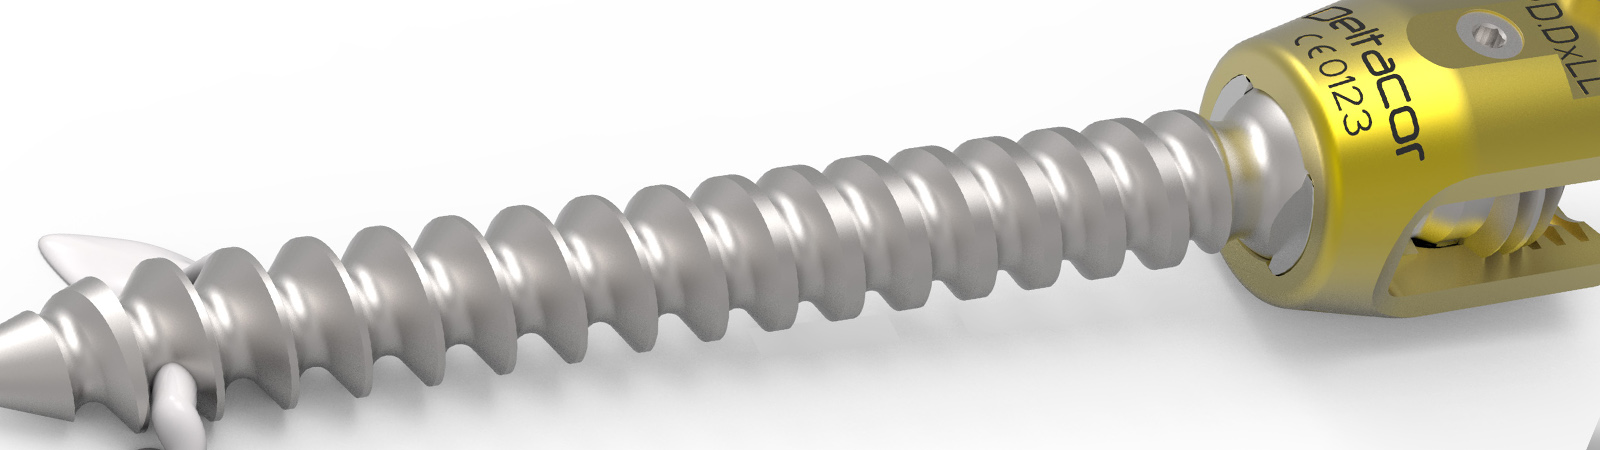

Reduziert auf zwei Instrumententrays, ermöglicht KINERA den flexiblen Einsatz aller Operationsmethoden. Degeneration, Trauma oder Deformität. KINERA bietet für alle Indikationen eine optimale Lösung.

KINERAPatentiertes Design

KINERA ist ein einzigartiges System auf dem Markt. Die Besonderheit liegt am Design des Schraubenkopfes. Medio-Lateral ist der Kopf schwenkbar. Kranio-Kaudal ist der Kopf fixiert. Durch den Einsatz einer Wippe im Schraubenkopf, welche sowohl den Stab von der unteren, als auch von der oberen Seite umschließt, wird die notwendige Flexibilität auch in Kranio-Kaudaler Ebene gewährleistet.

KINERA bietet nicht nur ein einzigartiges Schraubendesign, sondern auch die notwendigen Instrumente, die für degenerative Fälle, Deformitäten oder Trauma vielfältig einsetzbar sind. Besondere Aufmerksamkeit wurde bei der Zusammenstellung des Systems auf eine Reduktion der Instrumententrays gelegt. Alle Operationenmethoden können mit nur zwei Instrumententrays abgedeckt werden.

zurückKINERAPerkutane Fixation

KINERA hat seinen Stärken insbesondere in der Reposition von Frakturen. Auf simpelste Art und Weise kann perkutan durch das einzigartige Schraubenkopfdesign reponiert bzw. lordosiert werden. Keine zusätzlichen Instrumente für die Aufrichtung des Wirbelkörpers sind notwendig. Die Reposition wird ausschließlich durch eine Manipulation der perkutanen Hülsen erziehlt.

zurückKINERAAugmentation

KINERA erlaubt bei osteoporotischem Knochen durch seine Fenestierungen im Gewindekörper eine feste Verankerung der Pedikelschraube mittels Zementinjektionen.Der Zement wird direkt über Applikationshülsen durch die Kanülierung der Schraube eingebracht. Am distalen Ende des Gewindes tritt der hoch visköse Zement durch die Fenestierung langsam in den trabekulären Strukturen des Wirbelkörpers aus.